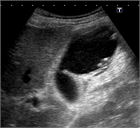

1. 急性胆嚢炎の原因の90~95%は胆嚢結石であり、結石の嵌頓による胆嚢管閉塞と胆嚢内胆汁うっ滞に引き続き、胆嚢粘膜障害が起こり、炎症性メディエーターの活性化が引き起こされる。